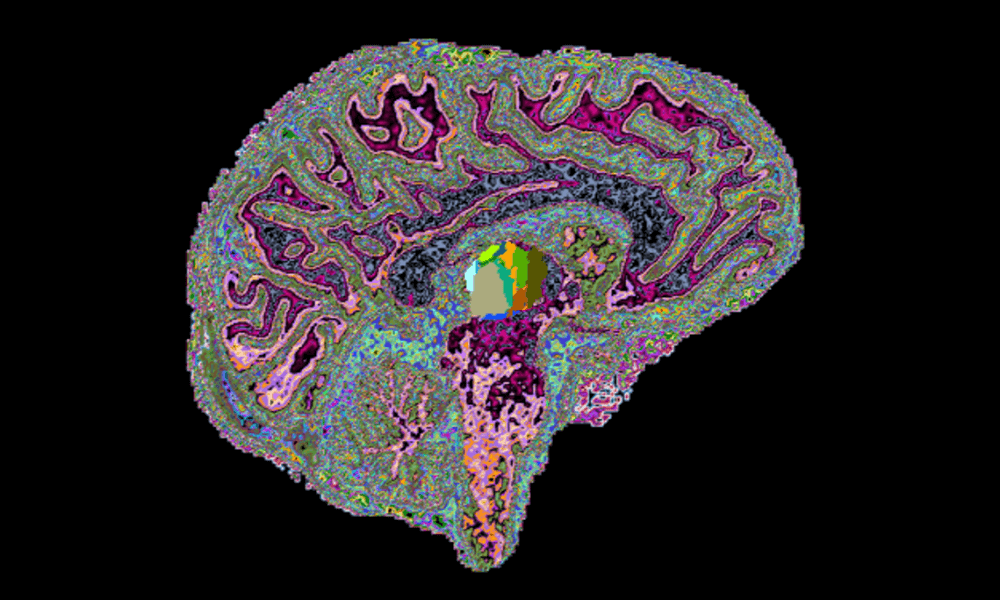

The Multiple Sclerosis (MS) Imaging Lab, directed by Eric Klawiter, MD, MSc, focuses on MS clinical research as well as the application and development of new imaging methods to better understand, diagnose and treat MS.

Through the use of novel imaging techniques, we examine changes in structural and functional brain networks in MS in relation to clinical outcomes such as cognition. The overall goal is to integrate novel imaging techniques into therapeutic clinical trials, which our lab is also involved with.

Our current imaging dataset consists of data from the 3T Connectom scanner and an ultra-high field 7T scanner on patients with MS including:

- Diffusion tensor imaging (DTI)

- Advanced diffusion imaging (i.e. Q-ball and axon diameter modeling)

Multi-modal Neuroimaging

The MS Imaging Laboratory is involved in various neuroimaging studies that implement established and novel techniques to examine structural and functional connectivity in relationship to cognitive dysfunction in MS.